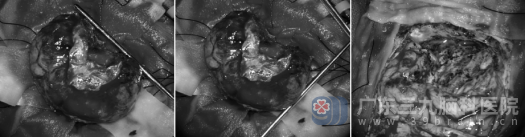

手术室里,一场无声的战役打响。在高清显微镜下,欧阳辉教授带领团队以毫米级的精度进行剥离。肿瘤质地韧,与脑膜粘连紧密,且血供极其丰富,每一步都需在出血与控制中寻找平衡。尤其当分离至紧贴上矢状窦的肿瘤基底时,气氛几乎凝固——这里血管密布,是手术中最危险的“雷区”。团队屏息凝神,以超乎寻常的耐心与细腻,一点一点地将肿瘤从血管壁上分离。三个半小时,如履薄冰,如临深渊,最终,肿瘤被完整摘除,所有重要血管和脑组织得以完好保留。